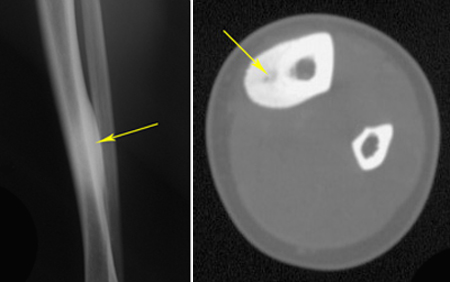

X-ray and CT scan of an osteoid osteoma in the tibia

(Left) This X-ray shows an osteoid osteoma in the tibia. (Right) A cross-section CT scan of the same tumor.